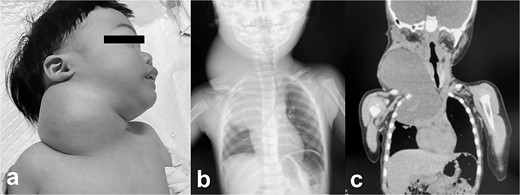

Intra- and post-operative findings from the first operation. (a) Intraoperative findings showed a huge bulge in the right neck. (b) A Denver shunt (peritoneovenous shunt) was inserted from the right cervical region to the abdominal cavity for volume reduction of the cervical cyst to prevent airway obstruction. Pump chamber with backflow prevention valve was implanted in the right anterior chest subcutaneous tissue. (c) Post-operative findings showed a reduction in the right neck swelling, even when crying. (d) The pressure on the trachea was shown to be relieved on the X-ray.

A male infant weighing 2726 g was born at 38 weeks of gestation. Antepartum ultrasonography and magnetic resonance imaging (MRI) revealed a right cervical cyst, suggestive of a lymphangioma. A right cervical cyst was noted at birth and gradually decreased in size thereafter. However, right cervical swelling became evident when he cried (Fig. 1a and b). An MRI obtained at 21 months of age showed a huge cyst in the right cervical mediastinal region. Following diagnosis of a lymphangioma with hemorrhage, he was treated with Eppikajutsuto®, a Japanese traditional Kampo medication, 2 g/d (0.2 g/kg). An MRI revealed tumor enlargement after oral administration of Eppikajutsuto® for 2 months. A complex vascular malformation was noted (Fig. 2) and the dose was increased to 5 g/day (0.5 g/kg). A repeat MRI 2 months after the dose increase showed no reduction in the size of the tumor. After another 4 months, the dose of Eppikajutsuto® was further increased to 7.5 g/d (0.65 g/kg). The tumor in the cervical region had enlarged further with an accompanying risk of airway system compression (Fig. 3a–c). A puncture and suction of the lymphangioma was performed for volume reduction and the content was prepared for bacterial culture. The content was dark red in color, which was consistent with hemorrhage. The white blood cell count (WBC) was 19 190/μl and the C-reactive protein (CRP) concentration was 5.77 mg/dl. He was admitted to the hospital to undergo treatment with intravenous and oral antibiotics. The bacterial culture results were negative. On the 22nd day of hospitalization, the WBC count was 8780/μl and the CRP concentration was 0.39 mg/dl. On the 24th day of hospitalization, a Denver shunt was inserted from the right cervical region to the abdominal cavity to reduce the volume of the cervical cyst to prevent airway obstruction (Fig. 4a–c). A pump chamber with a backflow prevention valve was implanted in the right anterior chest subcutaneous tissue (Fig. 4b). By applying pressure to the chamber, the cyst fluid in the neck was returned to the abdominal cavity. The patient was discharged on the 6th post-operative day. The swelling in the right neck was reduced and the pressure on the trachea was relieved based on the X-ray findings (Fig. 4c and d). On the 5th day after hospital discharge, the patient was febrile and the right neck swelling recurred. A hemogram revealed severe anemia and bleeding within the neck cyst was suspected. He was readmitted to the hospital and on the 2nd day after admission the cervical cyst was punctured, which yielded bloody contents. A transfusion was performed for anemia secondary to hemorrhage in the neck cyst. Sirolimus (1 mg), a mammalian target of rapamycin inhibitor, was added 7 months after starting Eppikajutsuto® due to a concern that administration of a Kampo medication and insertion of the Denver shunt might not be effective. An X-ray showed that the tip of the catheter may have moved within the cyst, which caused the catheter tip to penetrate the cyst and resulted in bleeding within the neck cyst (Fig. 5a). Serial MRI findings showed that the old bleeding site was within the mediastinal region of the lymphangioma. Revision surgery was performed 3 weeks after inserting the Denver shunt. Intraoperative findings showed that the tip of the catheter had penetrated the cyst wall (Fig. 5c). There were cyst walls with a septum on the mediastinal side of the cyst and when incised old bleeding was noted and the walls were opened as much as possible (Fig. 5d). The tip of the catheter was rounded and fixed with threads. The catheter was returned to the cyst and the wound was closed (Fig. 5b). The patient was discharged 9 days after the 2nd surgery. The concentration of sirolimus on the 14th day of administration was 9.9 ng/mL (normal range: 5–15 ng/ml). On the 16th day after the second hospital discharge, the neck had enlarged, the surgical wound was erythematous, and discharge was noted at the site of the pump chamber. Bacterial cultures of the punctured the neck cyst content and the wound discharge grew Staphylococcus aureus. On the 24th day after the 2nd hospital discharge, the blood concentration of sirolimus 1 month after starting oral administration was 19.7 ng/ml. Therefore, the oral administration of sirolimus was temporarily discontinued. At the same time the patient developed a high fever and the 3rd operation was performed to remove the Denver shunt due to a catheter infection. The blood concentration of sirolimus 6 days after discontinuation was 1.4 ng/ml. An MRI on the 6th post-operative day from the 3rd operation revealed two different intensities in the neck and mediastinal regions where the Denver shunt was inserted (Fig. 6a). On the 10th day after the 3rd operation, the patient was discharged from the hospital but laboratory testing showed an elevated WBC count (13 250/μl) and CRP concentration (6.03 mg/dl). Three months after the 3rd hospital discharge, the right neck swelling abruptly decreased in size and the WBC count and the CRP concentration decreased to the normal range. An MRI 2 months after the 3rd operation showed that the mediastinal lesion was smaller with near-complete regression (Fig. 6b). The neck swelling was minimal 6 months after the 3rd operation. An X-ray showed no tumor shadow and no compression of the trachea by the lymphangioma (Fig. 6c) and magnetic resonance angiography (MRA) showed that the lymphangioma had regressed (Fig. 6d). Currently, no right cervical swelling is evident when the patient cries (Fig. 6e and f) and he is doing well with oral administration of Eppikajutsuto® (7.5 g/d [0.65 g/kg]).